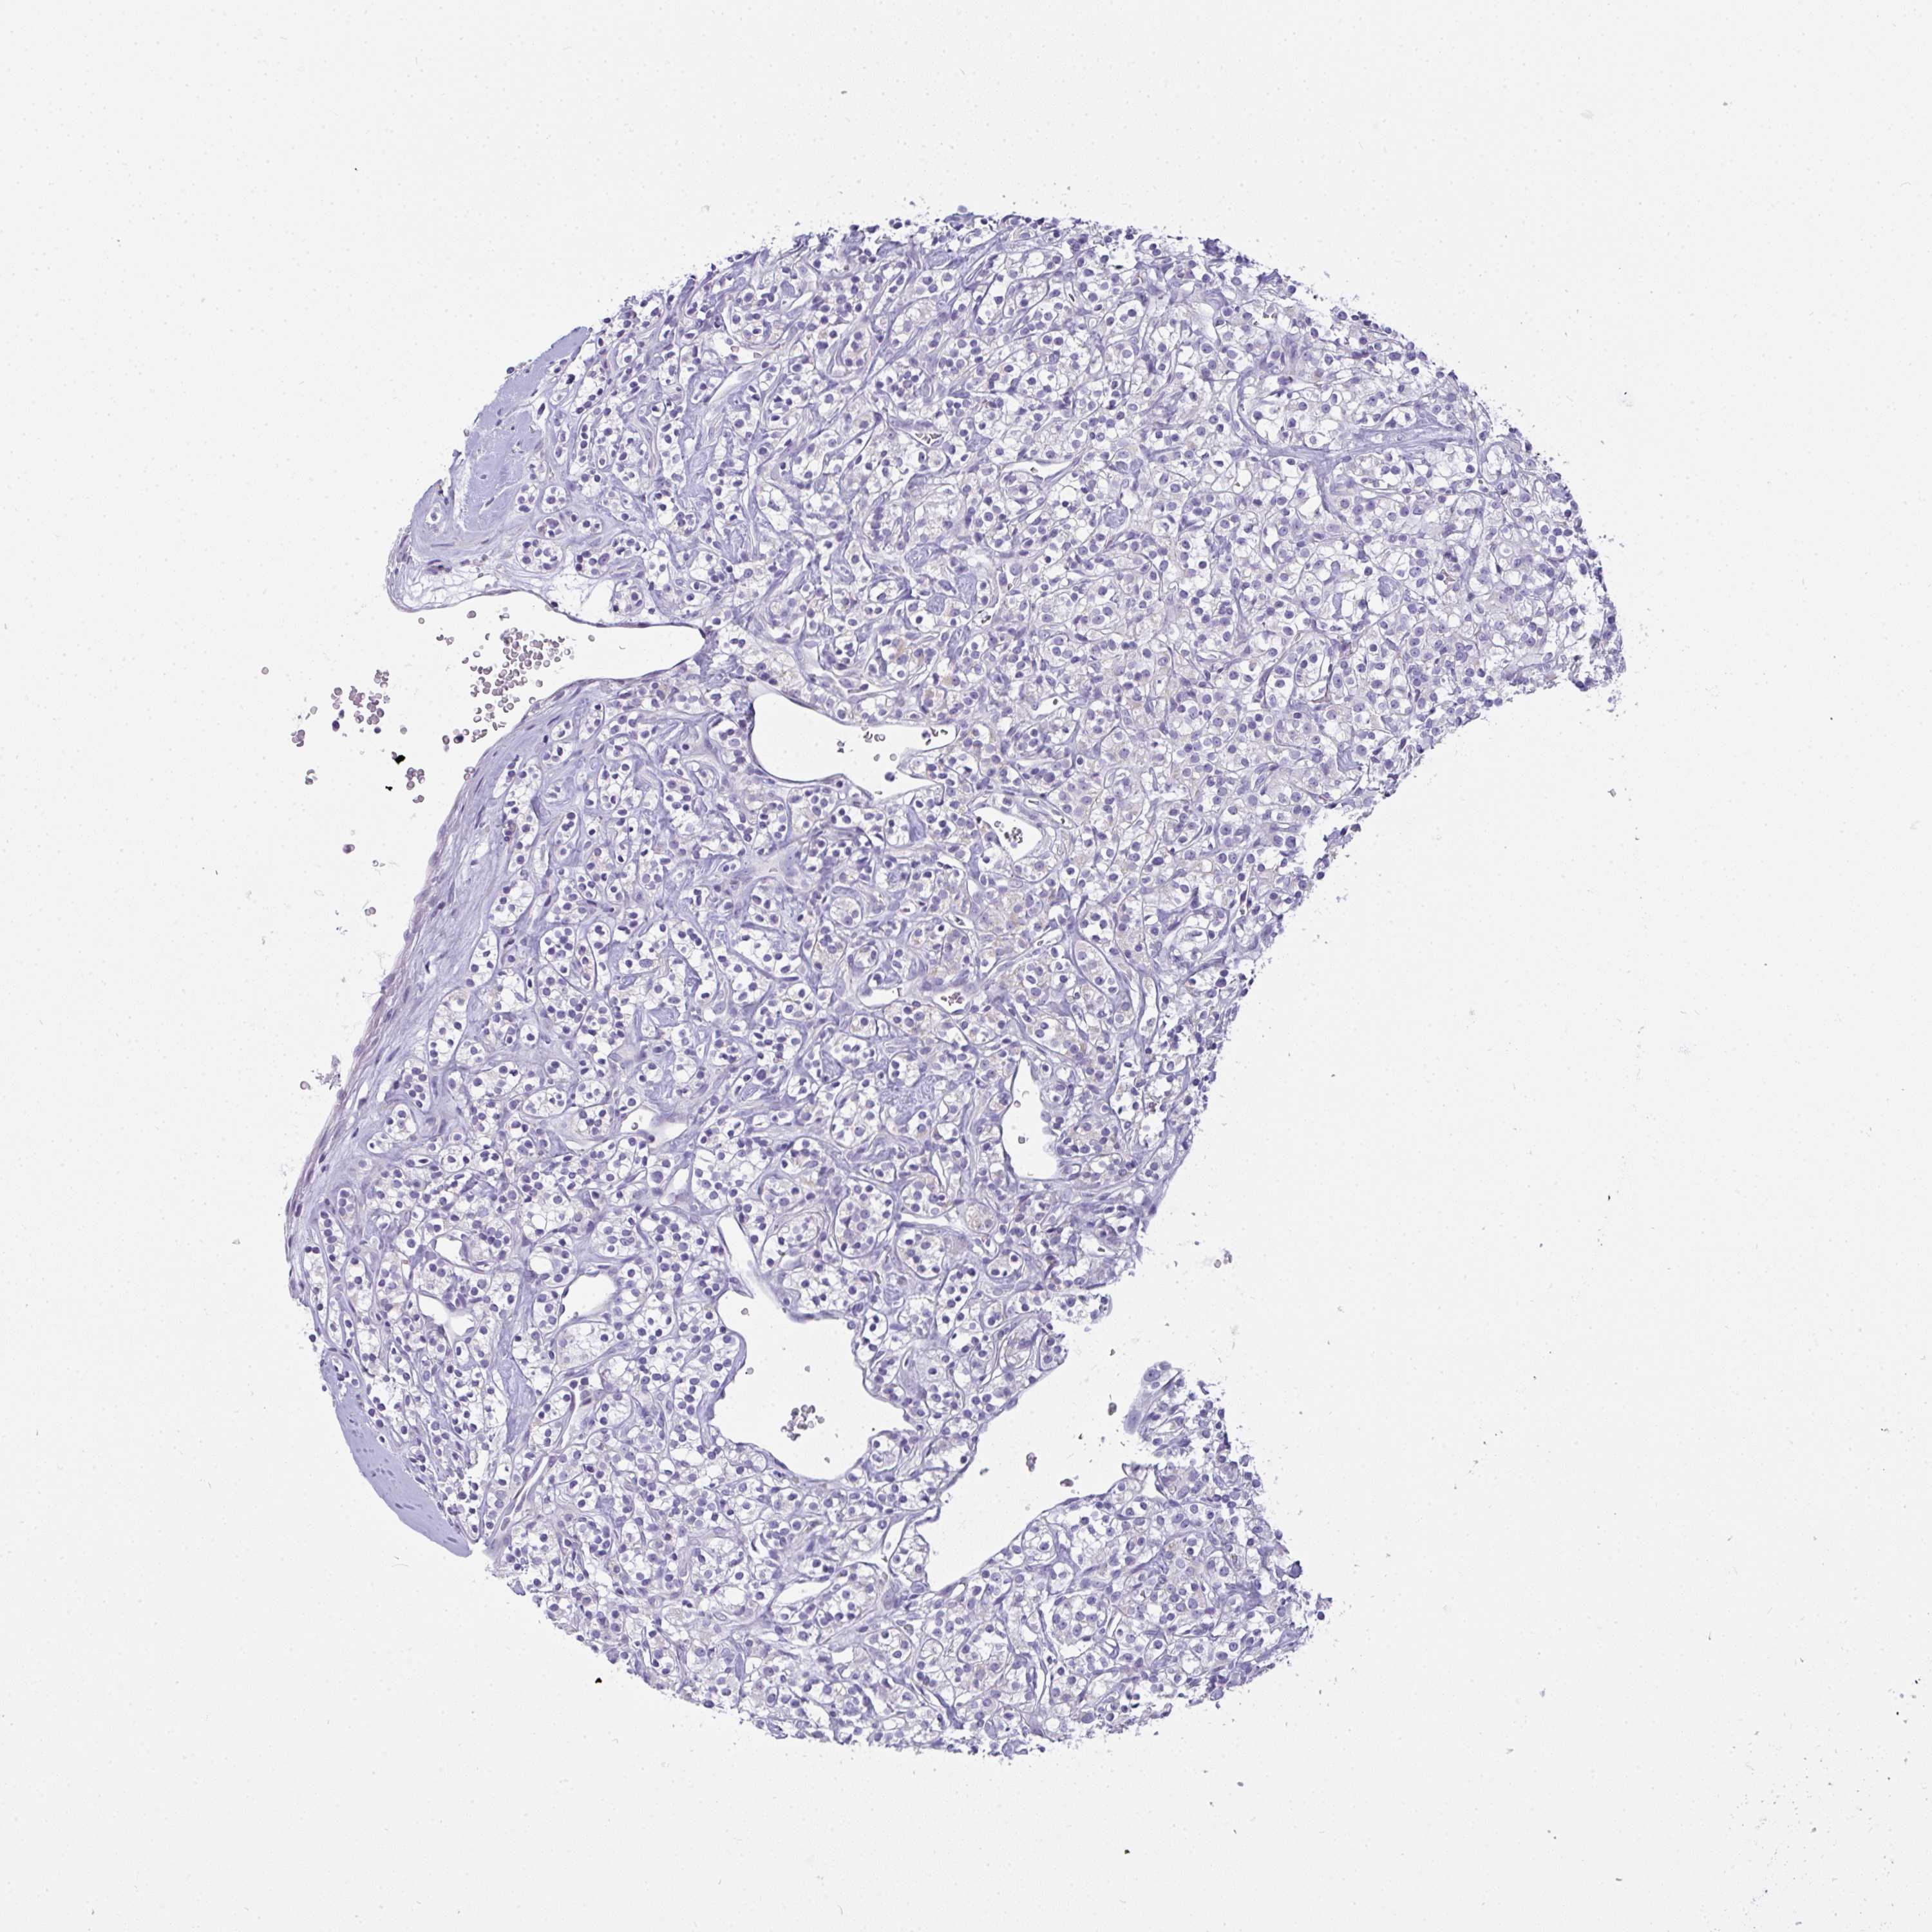

CANCER RENAL CANCER Show tissue menu

KICH TCGA KIRC TCGA KIRC VALIDATION KIRP TCGA PROTEIN RCC CPTAC PROTEIN EXPRESSION

KIDNEY CHROMOPHOBE (TCGA) - Interactive survival scatter ploti

The Survival Scatter plot shows the clinical status (i.e. dead or alive) for all individuals in the patient cohort, based on the same data that underlies the corresponding Kaplan-Meier plots. Patients that are alive at last time for follow-up are shown in blue and patients who have died during the study are shown in red.

The x-axis shows the expression levels (FPKM) of the investigated gene in the tumor tissue at the time of diagnosis. The y-axis shows the follow-up time after diagnosis (years). Both axes are complimented with kernel density curves demonstrating the data density over the axes. The top density plot shows the expression levels (FPKM) distribution among dead (red) and alive patients (blue). The right density plot shows the data density of the survived years of dead patients with high and low expression levels respectively, stratified using the cutoff indicated by the vertical dashed line through the Survival Scatter plot. This cutoff is automatically defined based on the FPKM cutoff that minimizes the p-score. The cutoff can be changed by dragging the vertical line or by entering a cutoff value in the square labeled "Current cut-off".

Under the Survival Scatter plot the p-score landscape (black curve; left axis) is shown together with dead median separation (red curve; right axis). Dead median separation is the difference in median mRNA expression between patients who have died with high and low expression, respectively. It is calculated as follows: median FPKM expression of dead patients with high expression - median FPKM expression of dead patients with low expression. This is intended to aid the user in visually exploring custom cutoffs and the associated p-scores and dead median separation.

Individual patient data is displayed and can be filtered by clicking on one or more of the category buttons on the top of the page. Categories describing expression level and patient information include: high, low, alive, dead, female, male and tumor stages. The scale of the x-axis can be toggled between linear and log-scale by clicking on the "x log" button. Mouse-over function shows TCGA ID, patient information and mRNA expression (FPKM) for each patient.

& Survival analysisi

Kaplan-Meier plots summarize results from analysis of correlation between mRNA expression level and patient survival. Patients were divided based on level of expression into one of the two groups "low" (under cut off) or "high" (over cut off). X-axis shows time for survival (years) and y-axis shows the probability of survival, where 1.0 corresponds to 100 percent.

GSDMB is not prognostic in Kidney Chromophobe (TCGA)